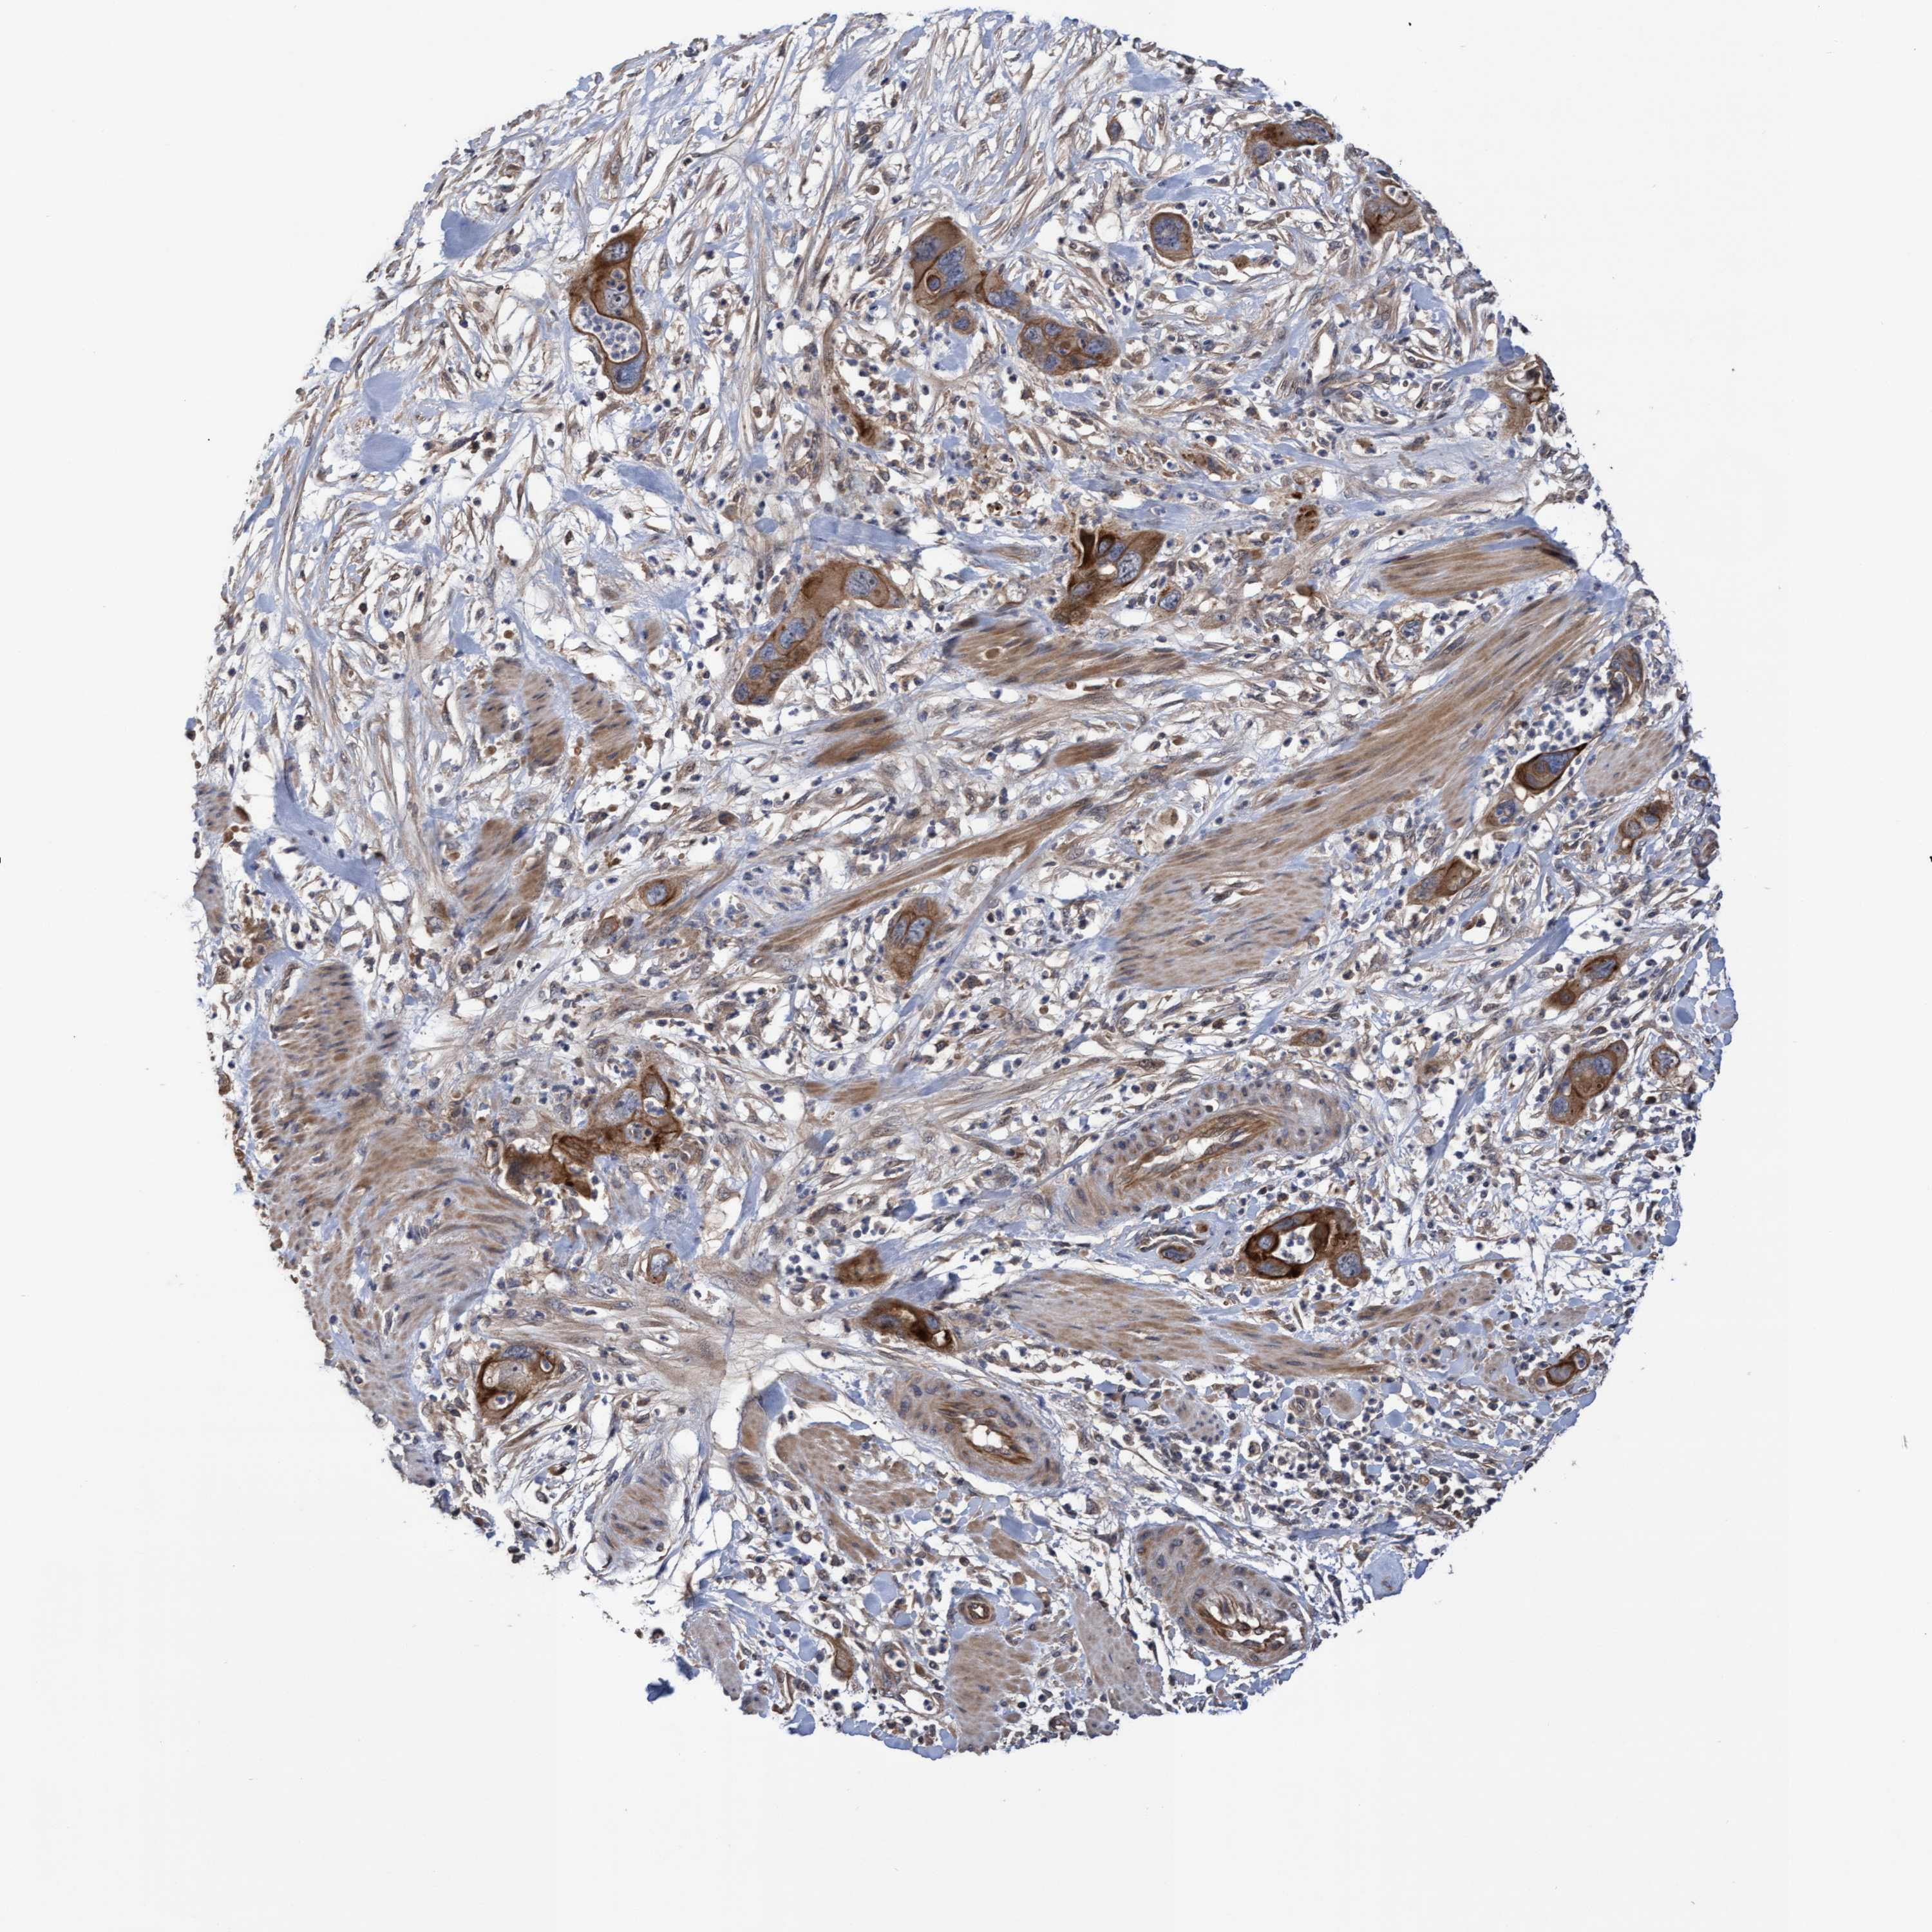

PANCREATIC CANCER - Protein expressioni

A mouse-over function shows sample information and annotation data. Click on an image to view it in a full screen mode. Samples can be filtered based on level of antibody staining by selecting one or several of the following categories: high, medium, low and not detected. The assay and annotation is described here.

Note that samples used for immunohistochemistry by the Human Protein Atlas do not correspond to samples in the TCGA dataset.

Antibody stainingi

Antibody staining in the annotated cell types in the current human tissue is reported as not detected, low, medium, or high, based on conventional immunohistochemistry profiling in selected tissues. This score is based on the combination of the staining intensity and fraction of stained cells.

Each image is clickable and will lead to virtual microscopy that enables deeper exploration of all samples and also displays staining intensity scores, fraction scores and subcellular localization as well as patient and tissue information for each sample.

Antibody HPA019033

Antibody HPA019167

Staining

High

Medium

Low

Not detected

Intensity

Strong

Moderate

Weak

Negative

Quantity

>75%

75%-25%

<25%

None

Location

Nuclear

Cytoplasmic/membranous

Cytoplasmic/membranous,nuclear

Adenocarcinoma, NOS